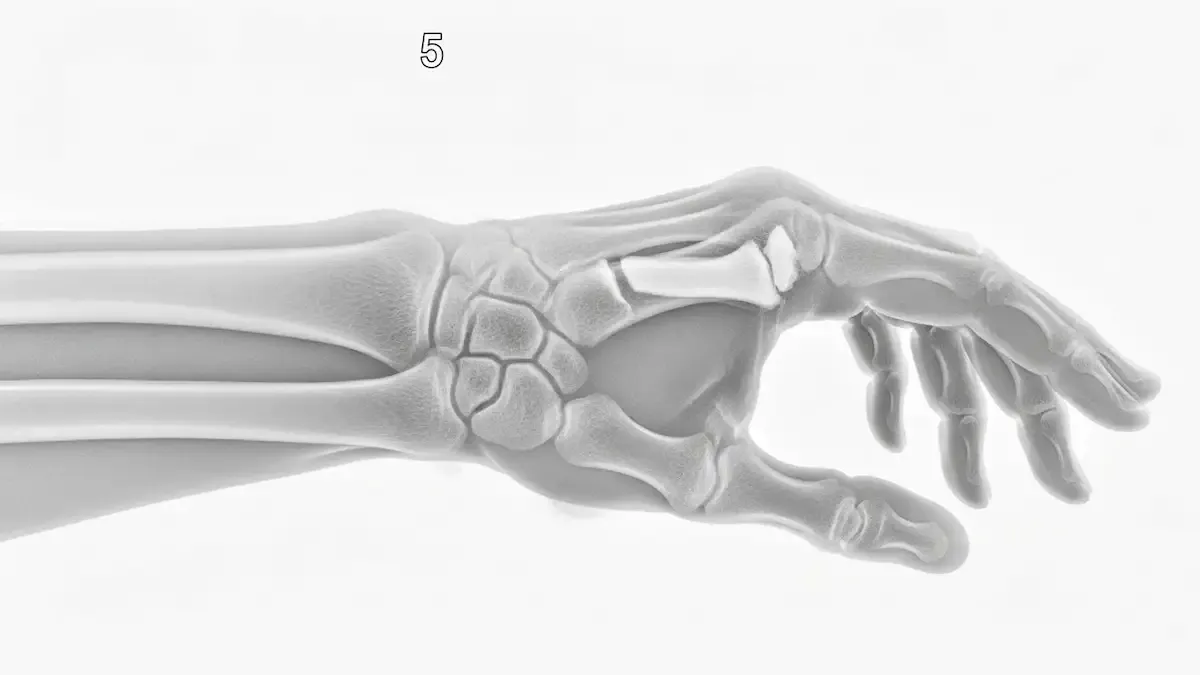

fraturas

Artigos sobre fraturas pelo Dr. Henrique Bufaiçal.